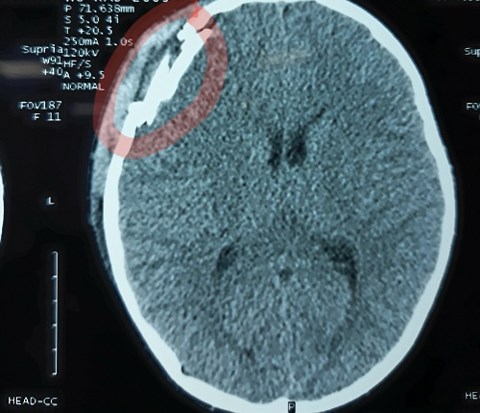

Hình ảnh chụp CT Scanner cho thấy sọ não cháu Điệp bị tổn thương nặng. |

Qua hình ảnh chụp phim CT Scanner cho thấy nạn nhân bị chấn thương sọ não, vỡ xương sọ vùng trán và tụ máu ngoài màng cứng.